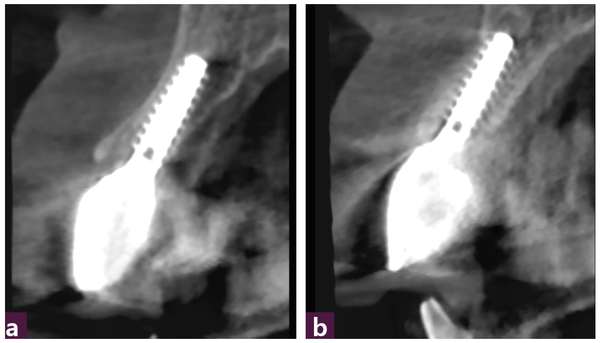

CBCT 진단에서 12번과 22번 치아의 협측 골 판과 구개측 골 판이 50% 이상 소실된 증등도 이상 치주질환임을 확인할 수 있다 [그림 3].

12, 22번 발치 후 GPS Drill을 이용해 구개측에 Magic Guide Pin을 삽입하고 [그림 4] CBCT 촬영 후 진단한 결과 12번은 순측의 gingiva에서 5.5mm, 22번은 순측의 gingiva에서 5 mm의 공간을 확보할 수 있었다.

Magic Guide Pin의 위치가 만족스러워 이를 바탕으로 임플란트 식립을 시뮬레이션 했고 식립 가능한 MagiCore는 직경 4.0, 길이 13mm, Magic Cuff 4로 예측됐다 [그림 5a, b].